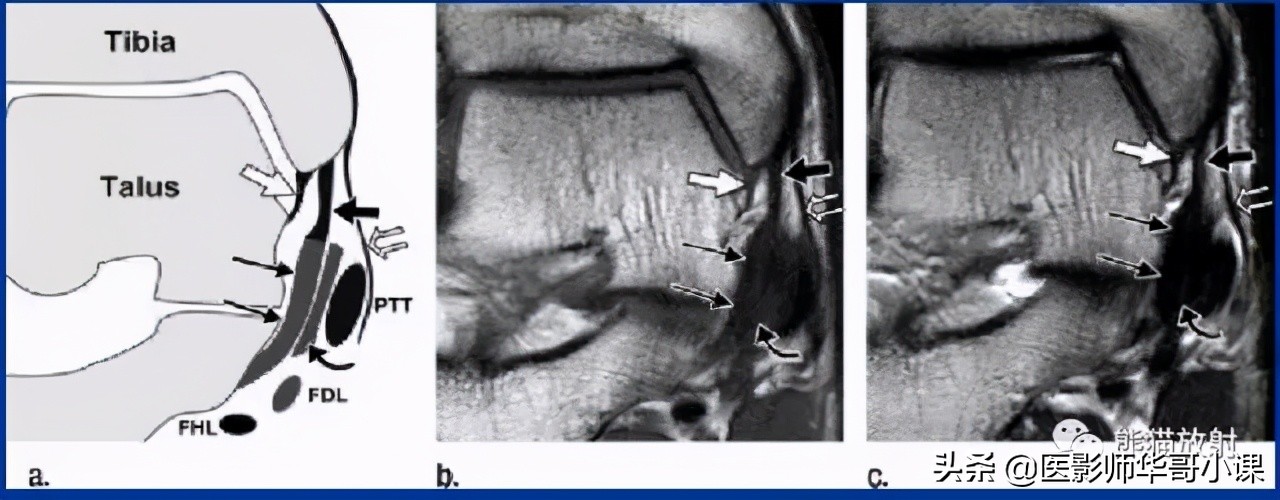

下胫腓联合韧带

胫腓骨远侧关节面由腓骨远端的凸面和胫骨远端的凹面组成,由胫腓韧带链接,关节内无软骨结构。 远端胫腓联合韧带由四部分韧带组成,包括: 骨间韧带,下胫腓前韧带,下胫腓后韧带,下横韧带。

骨间韧带由骨间膜远端增厚形成。下胫腓前韧带起于胫骨结节的前外侧,止于腓骨脊的前侧。下胫腓后韧带起于胫骨脊后侧,止于外踝后缘。下横韧带组成下胫腓后韧带的下半部分,可视为下胫腓后韧带的一部分。

下胫腓联合远端韧带结结构,包括:骨间韧带(IOL),下胫腓前韧带(AITFL),下胫腓后韧带(PITFL),下横韧带(ITL)。